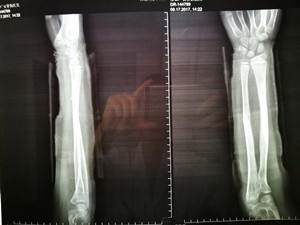

(整復(fù)前拍片)

看到女兒彎曲畸形的前臂,心疼不已的爸爸媽媽連忙抱起小女孩奔入附近的東港某骨科醫(yī)院。X線片顯示:左尺、橈骨骨折,骨折嚴(yán)重移位。這時(shí),媽媽首先想到的廣安醫(yī)院正骨科虞杰主任。之前,她曾在廣安醫(yī)院正骨科就診,對(duì)正骨科醫(yī)護(hù)人員的服務(wù)態(tài)度、服務(wù)質(zhì)量及醫(yī)療技術(shù)非常信任。